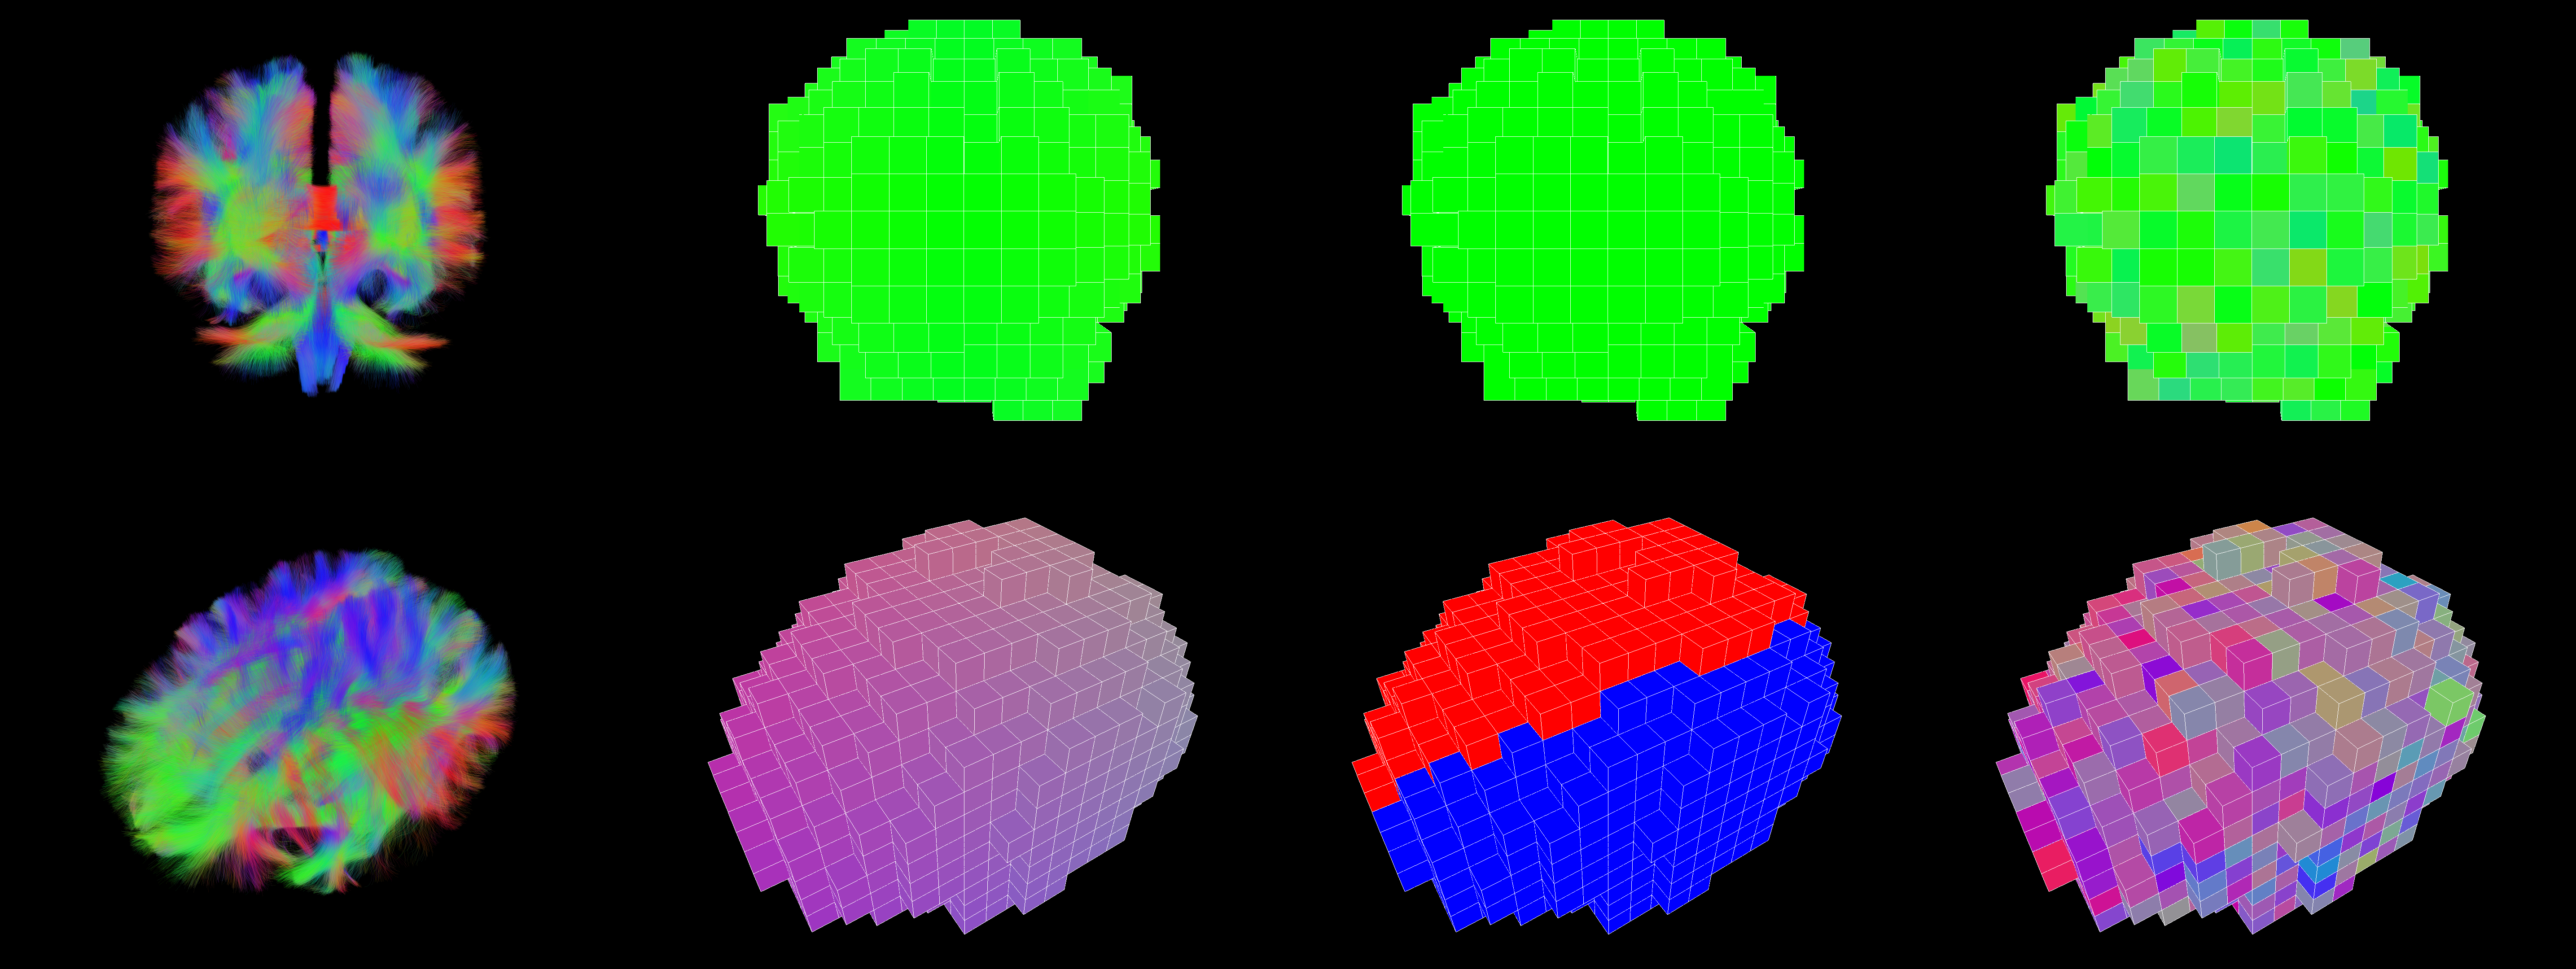

We propose a novel method for voxel-based streamline rendering that achieves fast, approximate order-independent transparency without relying on modern render pipelines and minimal preprocessing time. The first part of this method involves splitting the dataset into voxels, where each voxel stores streamline segments that pass through it as described in sections 2.1 and 2.2. Next, a mesh is generated for each voxel that connects the streamlines segments and renders the streamlines explained in Section 2.3. This mesh generation is performed once when reading the dataset. During rendering, we sort the voxels from back to front every frame, solving the most noticeable transparency issues. Furthermore, we extend this method by storing a set of precomputed line segment render orders per voxel and selecting the closest ordering based on the current view as described in Section 2.6 to improve the transparency accuracy within a voxel.

2.1 Voxelization

The algorithm takes a set of streamlines as input, where each streamline consists of a sequence of points. Our goal is to divide the dataset into voxels so that each voxel contains all line segments passing through it. In this paper, we define a voxel as a 3D cube with a fixed position and size. The size of the voxels used in this method differs from voxel sizes used in MRI scans or tractography algorithms. The voxels used in our method are an order of magnitude larger than the voxel sizes used in MRI scans to encompass more streamline points per voxel. To obtain the voxel coordinate of a streamline point , we first calculate its position relative to the dataset by subtracting the minimum bound , which is defined as the smallest coordinates contained in the dataset: . This ensures that each voxel has non-negative coordinates. The voxel coordinates are then obtained by dividing by the voxel size and taking the floor of the resulting vector: .